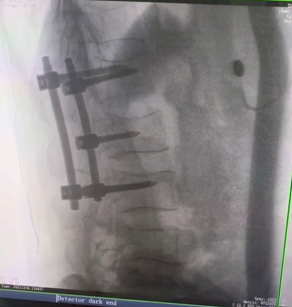

例如治療先天性脊柱側(cè)后凸畸形,由于脊柱自身復(fù)雜的解剖結(jié)構(gòu)限制,使得脊柱外科手術(shù)對(duì)于精確度有著較高要求。以往我們只能采用傳統(tǒng)的正側(cè)位圖像來(lái)判斷螺釘置入的位置,現(xiàn)在三維C形臂特有的類CT斷層成像,使得治療過(guò)程可視化,立體化,在術(shù)中非常直觀地判斷螺釘植入的準(zhǔn)確度。可有效引導(dǎo)術(shù)者植入后路螺釘并切除半錐體。同時(shí)可以在術(shù)中實(shí)時(shí)驗(yàn)證手術(shù)效果。有效地縮短了手術(shù)時(shí)間,降低手術(shù)風(fēng)險(xiǎn),避免了不必要的術(shù)后翻修手術(shù)。

另外,三維C形臂采用12英寸(30cm x 30cm)的平板探測(cè)器,成像區(qū)域大,有效成像面積比9英寸傳統(tǒng)影增提升了100%,可一次拍七節(jié)頸椎、五節(jié)腰椎、十二節(jié)胸椎、雙側(cè)骶髂關(guān)節(jié)、股骨頭及單側(cè)盆骨。